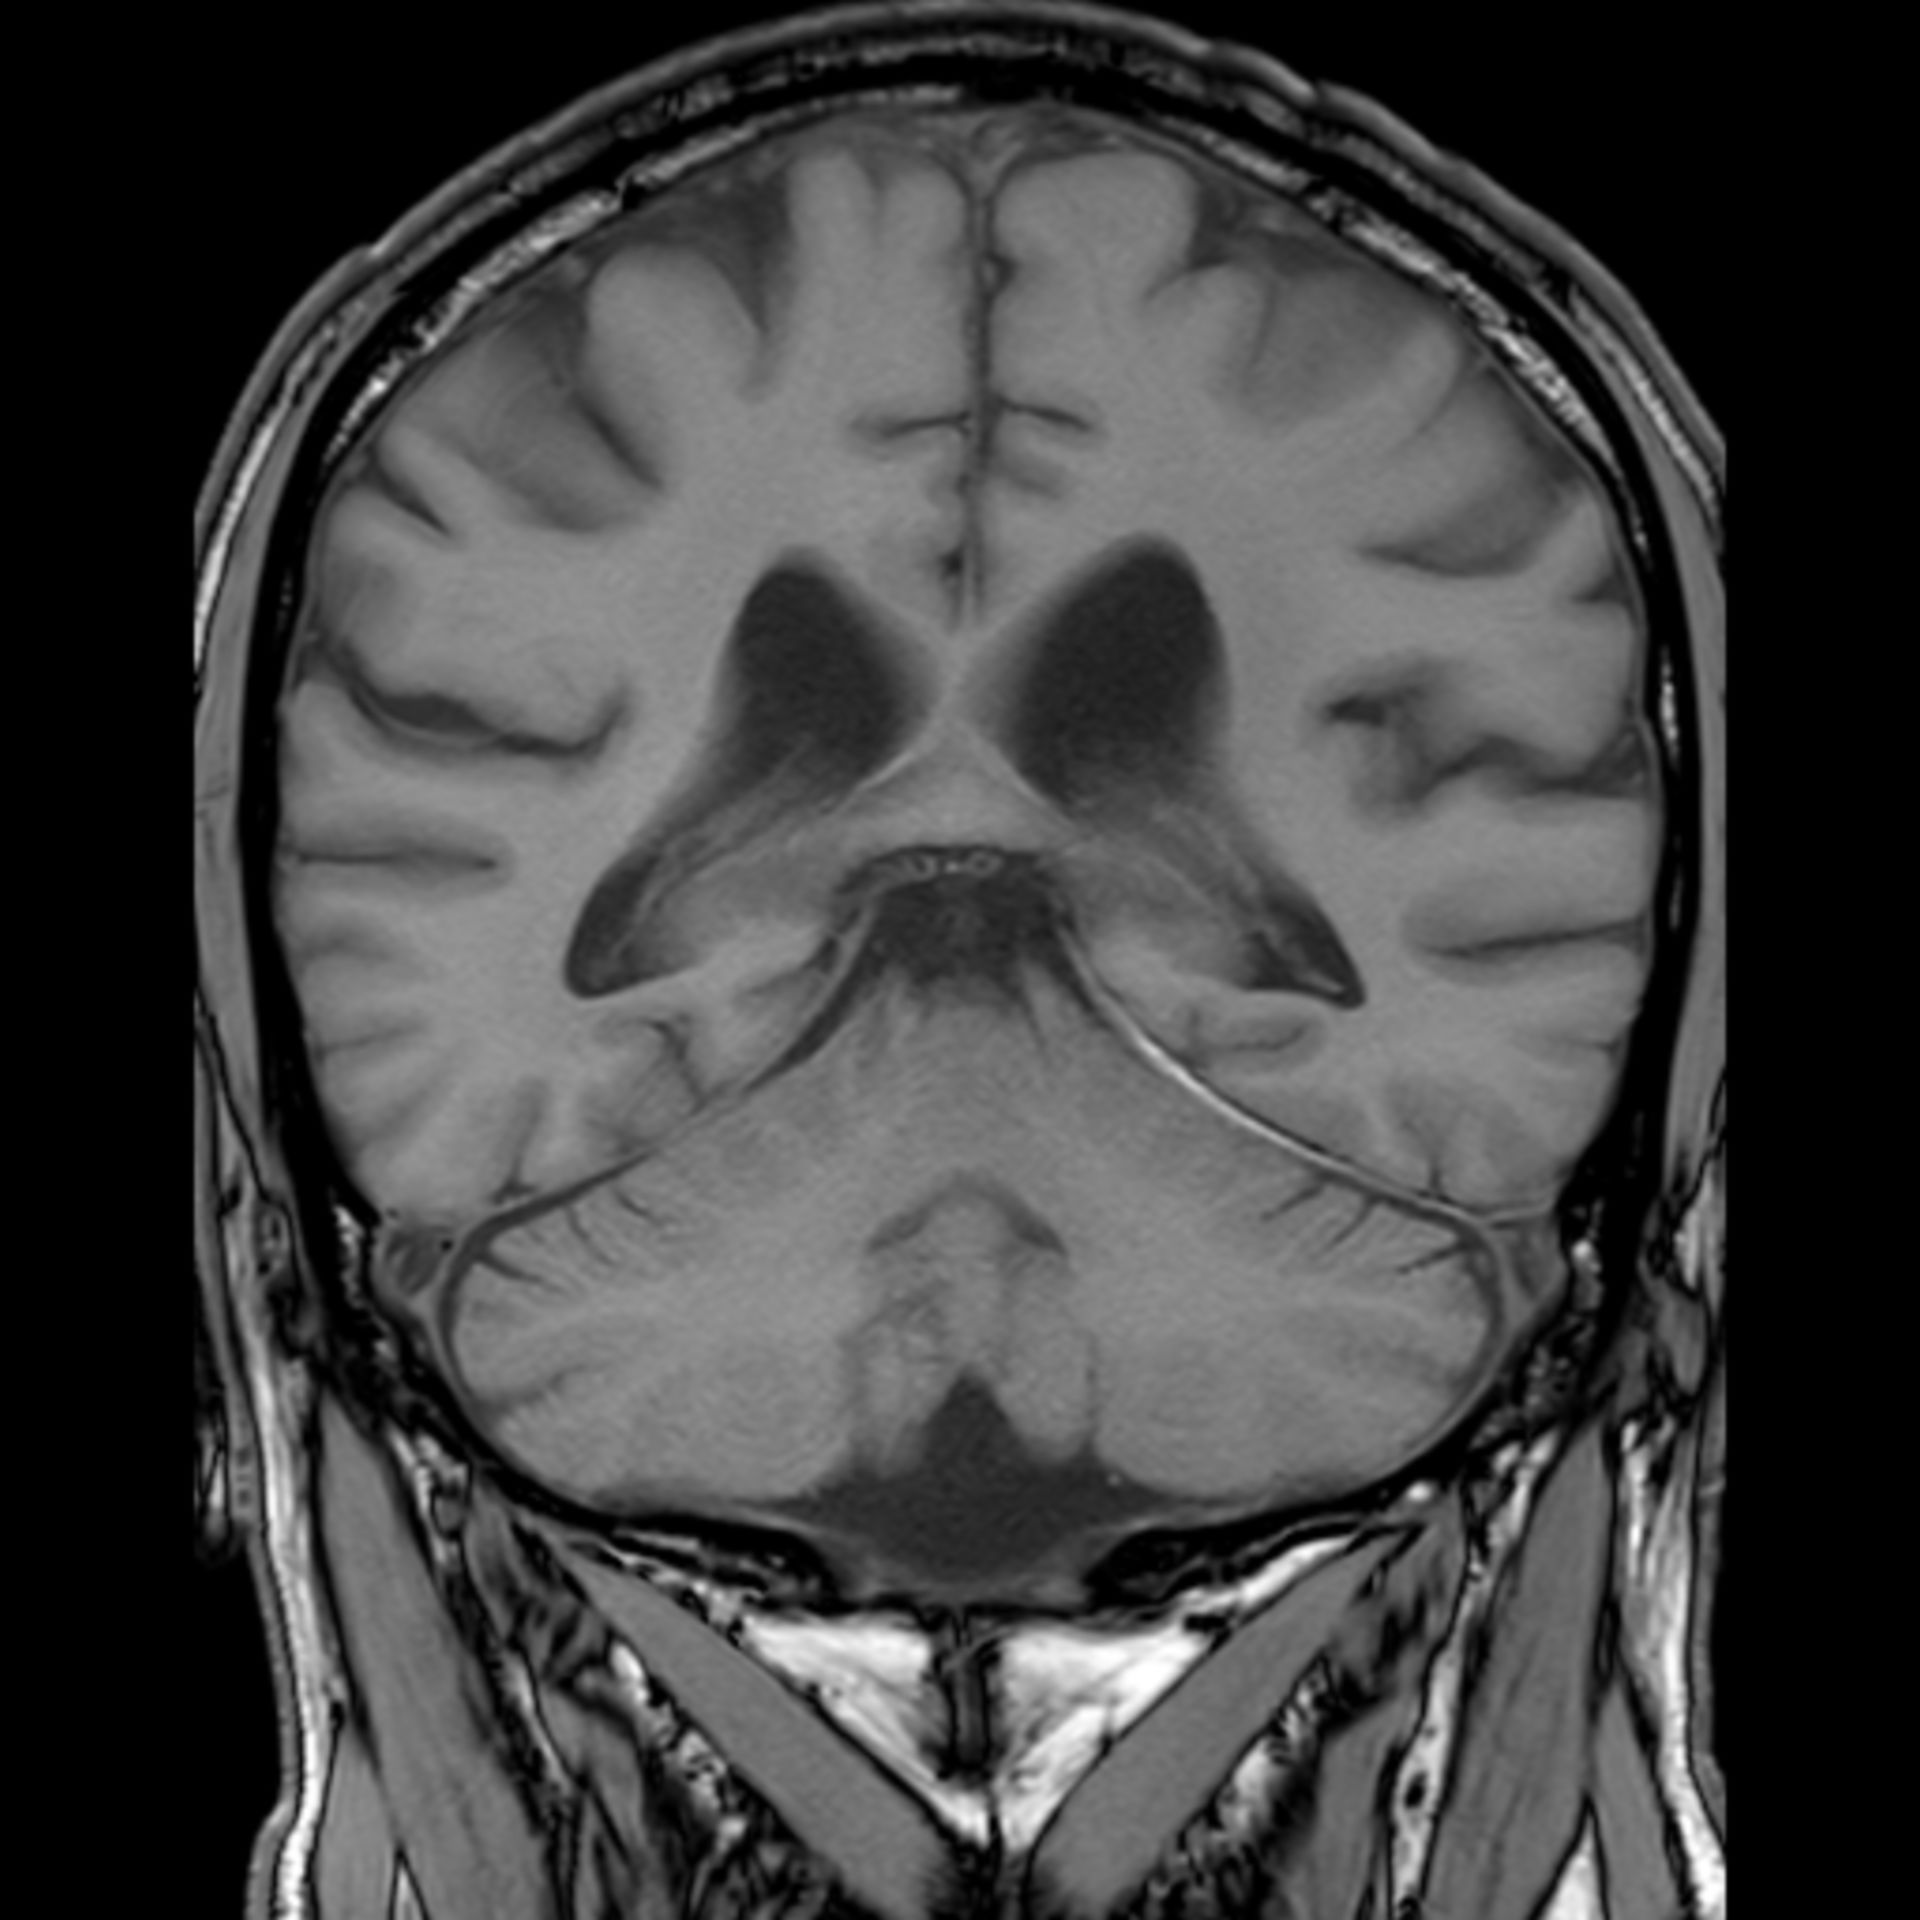

MRT Schädel – DocCheck MRT Bild, könnte das ein Tumor sein? Kennt sich jemand damit aus? Könnte die helle Fläche ein …

MRT Schädel – DocCheck Sichere Prostatavorsorge mittels MRT-Untersuchung der Prostata

MRT Schädel – DocCheck #MRT: Sungai Buloh – Kajang Line Phase 1 To Officially Start 16th December – Hype Malaysia

MRT 4 Schädel – DocCheck Taipei MRT Roadmap